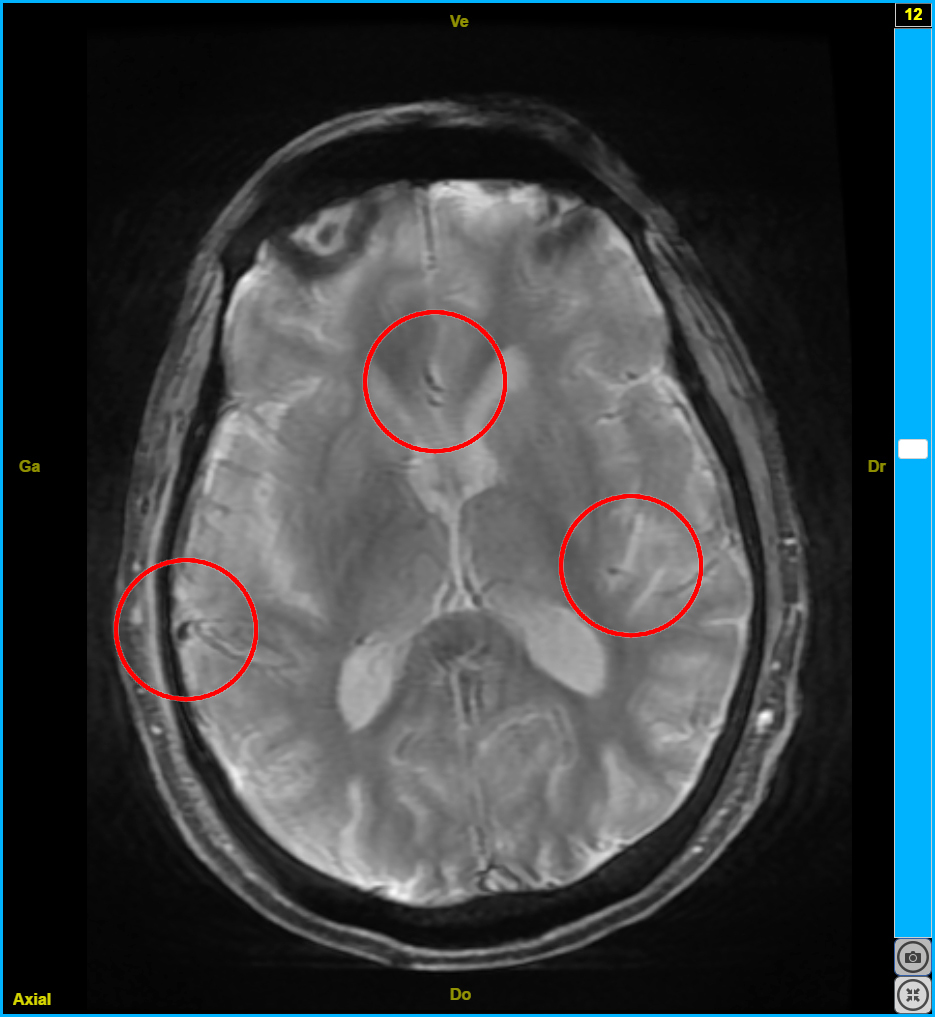

Neurosciences

Images et documents en rapport avec les articles

fiche3